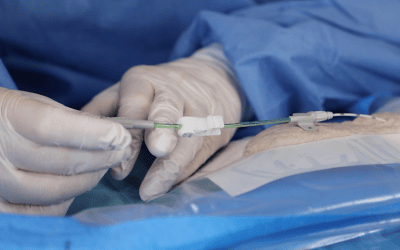

Colocación de una línea media

Una línea media se inserta con técnica Seldinger: es conocida en las UCI por ser el método de introducción de las vías centrales y de los catéteres arteriales.

La técnica Seldinger puede ser pura, simplificada o modificada.

Para ello, se necesita:

- una aguja de punción fina, en general de 21G

- una guía de acero inoxidable o de nitinol (material antiacodamiento)

- un dilatador que sirve únicamente para la dilatación o

- un microintroductor que consta de una vaina pelable y de in dilatador interno.

En este video podemos ver la colocación mediante la técnica Seldinger más sencilla: la Seldinger simplificada, para la que no se necesita dilatador. Especialmente indicada en pediatría ya que es rápida y muy poco invasiva

La ventaja de cualquiera de las técnicas Seldinger es que la aguja sirve solo para localizar la vena. La guía sirve para canalizar la vena y guiar el catéter. Se trata de la técnica “over the wire” = encima de la guía. Al no tener el catéter junto a la aguja, no se necesita canalizar en el momento de la punción, significa que el gesto se hace en varias etapas y de esta forma es mucho menos invasivo.

Se usa una aguja de calibre pequeño para poder minimizar el trauma a los tejidos. Sin embargo, el uso del dilatador es necesario cuando el diámetro del catéter es superior al orificio que crea la aguja. Sirve para ensanchar el paso subcutáneo.

• La técnica Seldinger pura es la técnica con dilatación

• La técnica Seldinger simplificada es la técnica sin dilatación

• La técnica Seldinger modificada (o MicroSeldinger) es la técnica con introductor pelable, que lleva en su interior un dilatador que se deja. Entonces se quita la guía y el dilatador interno. De esta forma, el introductor sirve de guía para insertar el catéter.